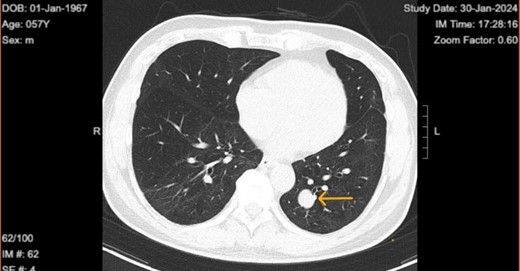

Upon diagnosis of SFT, the patient was referred to a surgeon for consideration for left lower wedge resection via video-assisted thoracoscopic surgery. However, the treatment consisted of monitoring of the tumor with biannual CT scans. Immediate surgical intervention was not performed, as the tumor remained stable in size, asymptomatic, and showed no signs of aggressive behavior. The latest CT on 30 January 2024 shows the tumor size to be 1.9 × 1.6 cm (initial size 1.5 × 1.3 on 21 May 2021) with no accompanying symptoms (Figs 2 and 3).

Chest computed tomography in 2024 shows well circumscribed solitary lung tumor of 1.9 × 1.6 cm in size.

Top image: Coronal view indicating the level of the solitary fibrous tumor (SFT). Bottom image: Axial CT scan at the indicated level, showing a well-circumscribed, homogeneous mass.